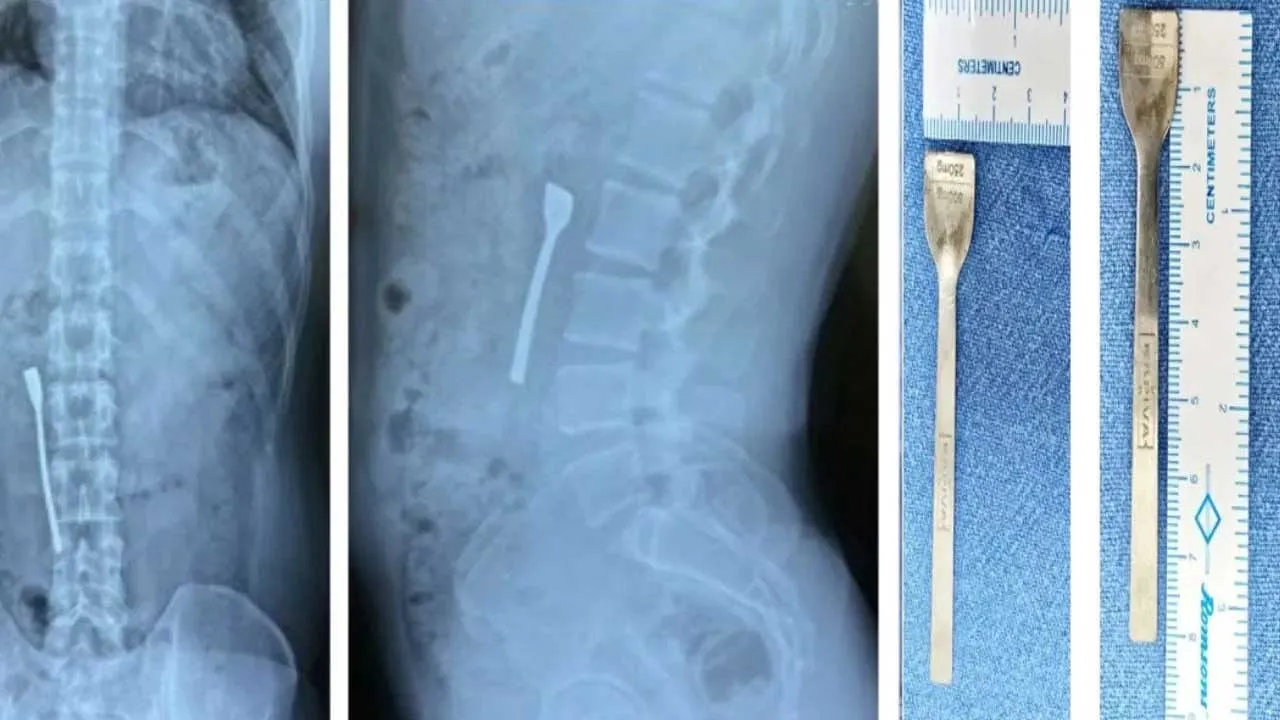

ડોક્ટરોએ માત્ર 30 મિનિટની એન્ડોસ્કોપી પ્રક્રિયા કરીને 30 વર્ષીય વ્યક્તિના આંતરડામાં ફસાયેલી 8 cmની ધાતુની ચમચી કાઢીને તેનો જીવ બચાવ્યો. આ દુર્લભ અને આઘાતજનક કિસ્સો તબીબી કટોકટીનું એક ઉત્તમ ઉદાહરણ છે, જેમાં ડોક્ટરોની ઝડપ અને વ્યવહારુ કુશળતાએ દર્દીને નવું જીવન આપ્યું.

ઉત્તર દિલ્હીની એક મલ્ટી-સ્પેશિયાલિટી હોસ્પિટલમાં પ્રારંભિક તપાસ પછી, દર્દીને ફોર્ટિસ શાલીમાર બાગના ઇમરજન્સી વિભાગમાં રિફર કરવામાં આવ્યો. દર્દીએ પેટમાં તીવ્ર દુખાવો અને અપચોની ફરિયાદ કરી હતી. હોસ્પિટલમાં પહોંચતાની સાથે જ, ડોક્ટરોએ તાત્કાલિક એક્સ-રે અને ડાયગ્નોસ્ટિક ઇમેજિંગ કર્યું, જેમાં ચોંકાવનારી સત્ય બહાર આવ્યું. તપાસમાં જાણવા મળ્યું કે, દર્દીના નાના આંતરડાના ઉપરના ભાગમાં 8 CMની ધાતુની ચમચી ફસાઈ ગઈ હતી.

ડૉ. રમેશ ગર્ગના નેતૃત્વમાં ડૉક્ટરોની ટીમે તાત્કાલિક કાર્યવાહી કરી. દર્દીને એનેસ્થેસિયા આપવામાં આવ્યું અને ઇમરજન્સી અપર ગેસ્ટ્રોઇન્ટેસ્ટાઇનલ (GI) એન્ડોસ્કોપી કરવામાં આવી. આ પ્રક્રિયામાં, એક પાતળી, લવચીક નળી (એન્ડોસ્કોપ)નો ઉપયોગ કરવામાં આવ્યો જેમાં કેમેરા અને પ્રકાશ હતો. સર્જિકલ ટીમે ફોર્સેપ્સની મદદથી ચમચીને કાળજીપૂર્વક આંતરડામાંથી બહાર કાઢી, તે પણ કોઈપણ આંતરિક ઈજા વિના. એવું કહેવામાં આવી રહ્યું છે કે, આ સમગ્ર પ્રક્રિયામાં ફક્ત 30 મિનિટનો સમય લાગ્યો.